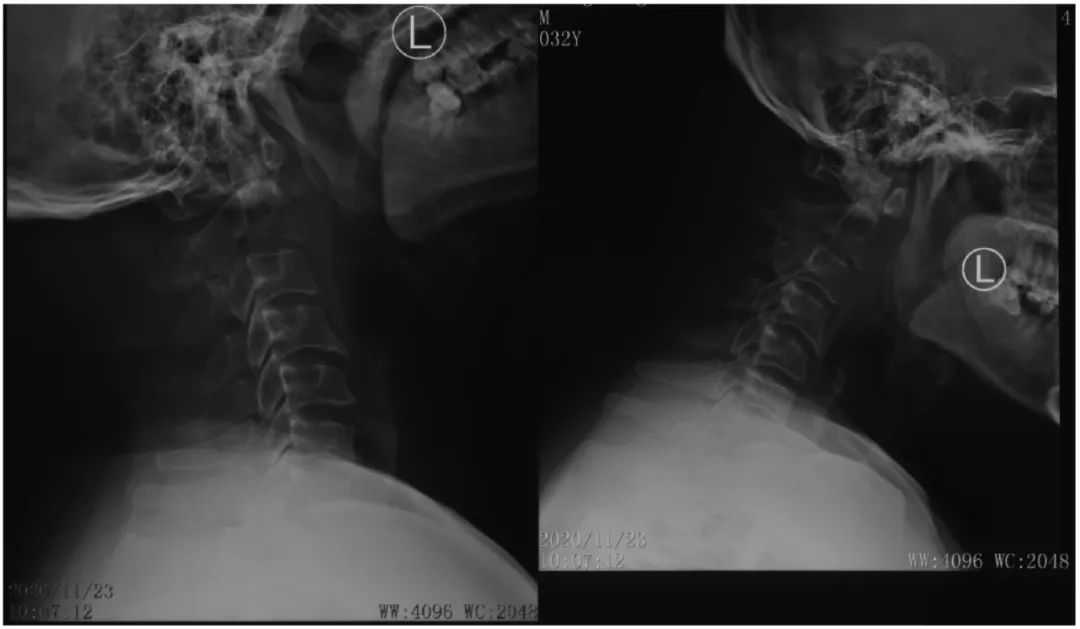

病史:male, 63 y/o

Neck pain for 3 months

影像资料:

诊断:C2椎体肿瘤